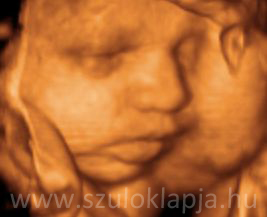

Már az anyaméhben érzik a simogatást

Az anyaméh optimális stimuláló környezet a magzat számára, teli változatos ingerekkel. A magzat sohasem izolált. A tapintás - az első eszköze az emberi tapasztalatszerzésnek és kommunikációnak - már az anyaméhben elkezdődik.

Az első testrészek - ahol a magzatnál kifejlődik a tapintás, mint érzékelés - azok, amelyek felnőttként is a légérzékenyebbek az érintésre. Az arccal kezdődik és a genitáliákkal, a nemi szervekkel folytatódik (10 hetes kor), majd az ujjak (11. hét), és a talp (12. hét) következnek. A 17. hétre a törzs is érzékennyé válik. A magzat megérinti arcát, ajkát, testrészeit, a köldökzsinórt, szopja a hüvelykujját. A 32. hétre a testének majdnem egésze érzékeny melegre, hidegre, nyomásra és fájdalomra. A baba érzékeli a hasfalon keresztül a simogatást.

UH fotók: Beleznay Katalin